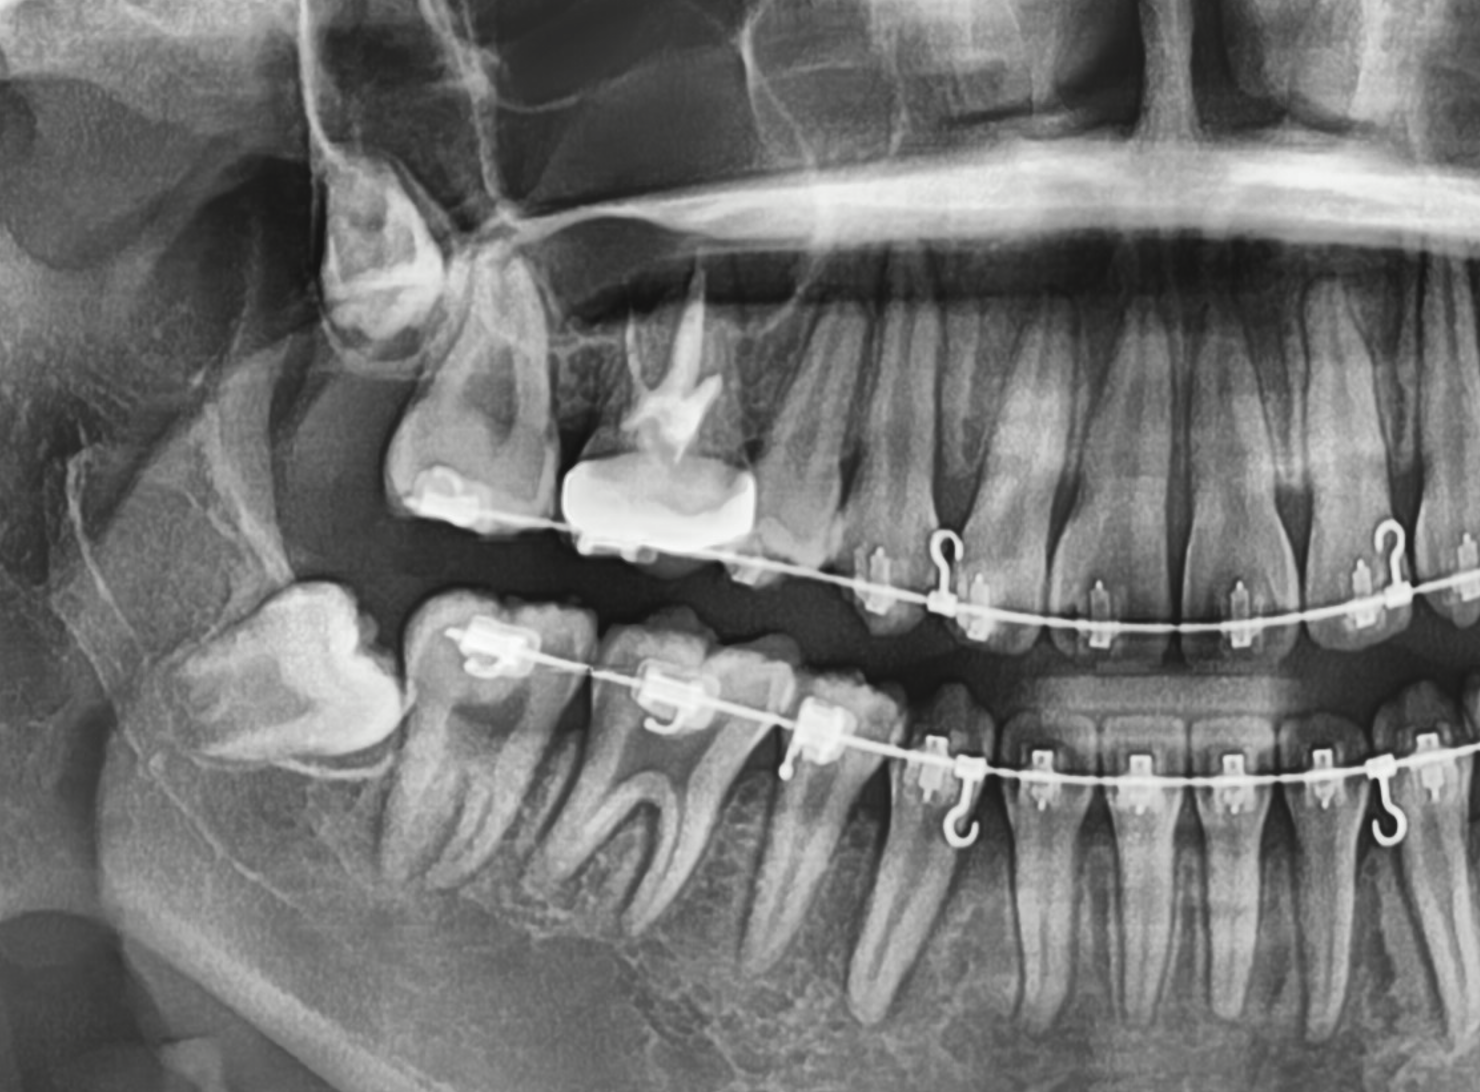

진단 및 검사

사랑니의 위치와 상태를 평가하기 위해 X-레이 촬영과 구강내 검진을 진행합니다.

환자에게 사랑니의 상태와 발치 필요성에 대해 설명하고, 발치 계획을 수립합니다.